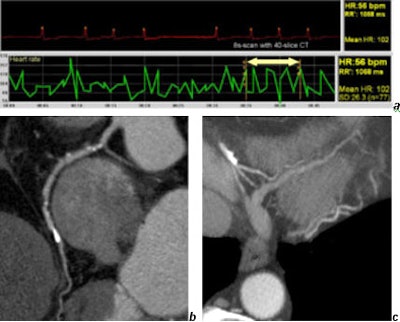

Another benefit is increased image quality even in challenging conditions, he said, showing a slide of a patient with vascular arrhythmia. Even though the patient's heart rate varied from 50-150 beats per minute (bpm) during the eight-second scan, the images clearly showed calcified soft plaque, and even small branches are nicely visualized.

![]() |

| Coronary CT in a patient with absolute arrhythmia (a) performed with 4 x 0.625-mm collimation. The heart rate varied from 40-140 bpm within the eight-second scan time. Note the soft plaques in the right coronary artery (b) and the good quality of small vessels (c). Images courtesy of Dr. Mathias Prokop. |